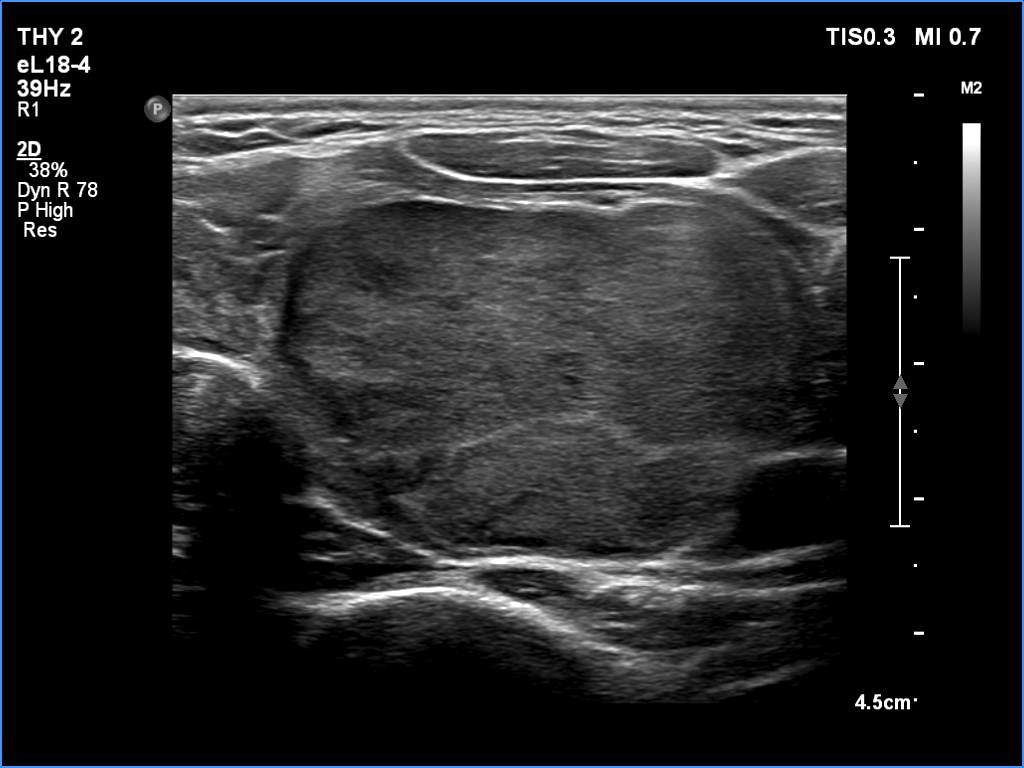

Histopathology disclosed minimally invasive follicular cancer. The largest diameter was measured 55 mm. Both capsular and vascular invasions were found microscopically.

Comments. It is worth highlighting three changes. First, the nodule echogenicity has changed over time - from clearly hyperechoic to moderately hypoechoic. Secondly, the nodule substantially increased in size. This is the cause for the disappearance of the halo, due to the nodule growth, the capsule became invisible thin. Thirdly, the pattern of the intranodular hypoechoic parts has also changed.